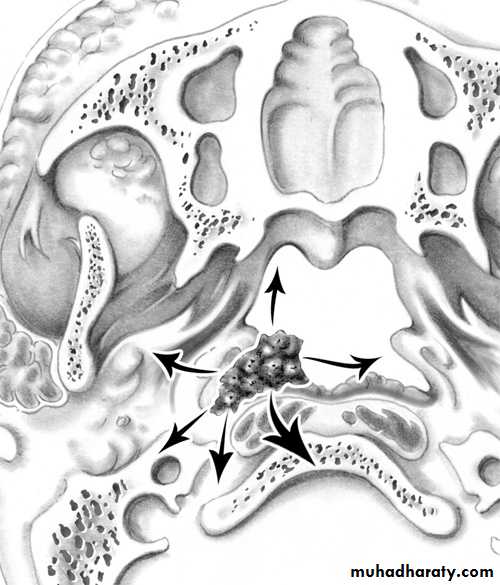

• Spread of Nasopharyngeal Carcinoma

• Direct, lymphatic (cervical L.N.) and blood borne (rare)

• -Anteriorly into the nasal cavity and paranasal sinuses leading to nasal symptoms.

• -Posteriorly to the retropharyngeal space and lymphnodes of Rouviere.

• -Laterally into the parapharyngeal space involving the last 4 cranial nerves.

• -Superiorly through the base of skull involving the optic nerve and the cavernous sinus.

• -Inferiorly to the oral cavity and retrotonsillar region

Spread of NP Carcinomma